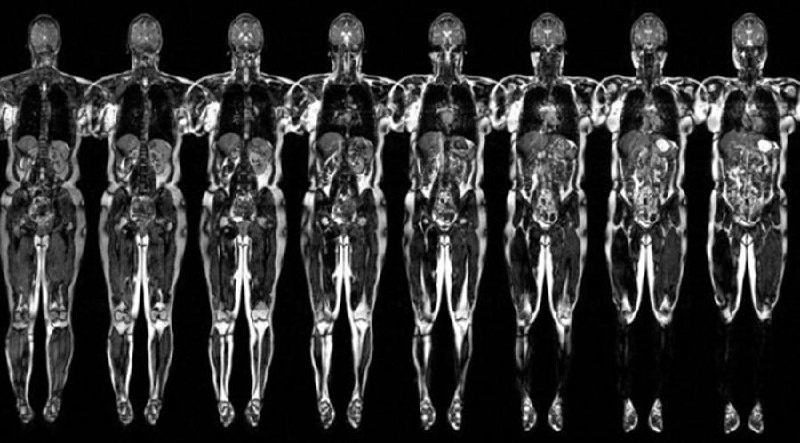

Что проверяют на МРТ? МРТ может проверить почти всё, кроме костей и лёгких: головной мозг (МРТ выявляет 95-99% патологий головного мозга), сердце и сосуды, суставы и позвоночник (при обследовании позвоночника точность достигает 93%, что выше, чем у рентгена и КТ), органы малого таза, органы брюшной полости, ЛОР-органы и мягкие ткани.